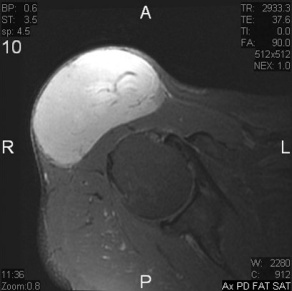

Dermatofibrosarcoma Protuberans